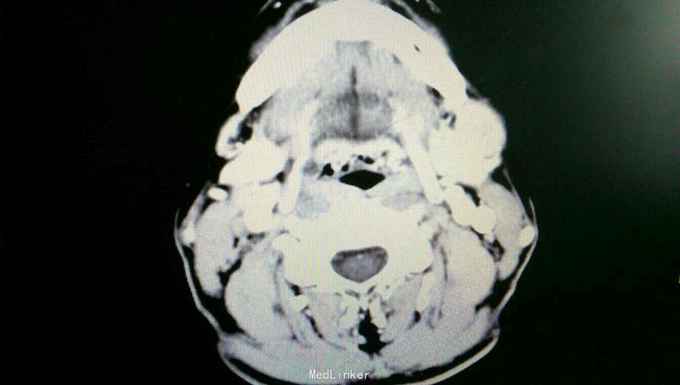

患者入院后,拟行左颌下肿块切除,在术前检查,术前准备时,常规胸片发现右侧肺部肿块,进一步行颈部及胸部ct检查,提示左颌下淋巴结肿大,转移性可能。右下肺周围性肺癌伴右肺门及纵膈多发淋巴转移考虑。决定先行左颌下肿块切除,明确诊断。术后病理示:左(左颌下腺)淋巴结转移性癌,来源首先考虑为肺。患者及家属考虑为晚期肿瘤,拒绝进一步手术治疗及化疗,下颌部切口愈合拆线后,出院。